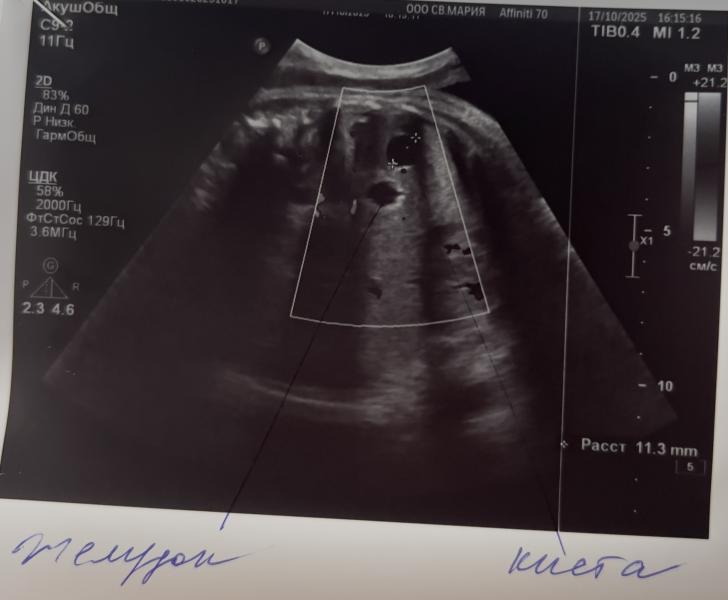

В 36.6 недель были с мужем на узи, хотела контрольно посмотреть все ли в порядке и прикинуть рос/вес. Из неожиданного врач сказала, что есть что-то типо кисты, которую надо будет наблюдать после родов, они случаются у детей в утробе и размер благо небольшой, повода для переживаний нет, чаще всего они за 2-3 месяца рассасываются после рождения. Нооо у меня возник вопрос… раньше на узи это замечено не было и как бы мы после родов могли бы узнать, что у малыша надо контролировать какую-то кисту? Им же после рождения не делают узи всех органов, а что если она начнет увеличиваться, а мы бы и не знали? Получается узи никогда лишним не бывает?)

Кисты где? В желудке ? Ну вообще конечно это все надо обследовать потому как вот допустим кисты в легких это порок развития который нужно оперировать, поэтому сходите на узи к Виноградовой которая скринингы в пц проводит